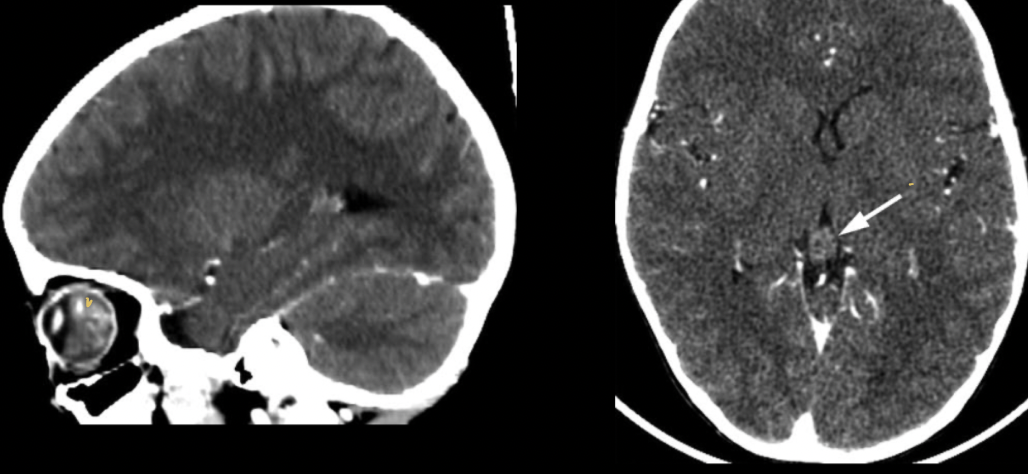

Hallazgos que podemos encontrar en una TC de orbitopatía tiroidea

• Agrandamiento de los músculos extraoculares

• Áreas de baja densidad debido a depósitos de glucosaminoglicano

• Exoftalmos

• Nervio óptico estirado

¿qué enfermedad sospechas?

orbitopatía tiroidea

¿Qué características esperas encontrar en una RM en secuencia T1 en la enfermedad de orbitopatía tiroidea?

Agrandamiento de músculos extraoculares

¿Qué características esperas encontrar en una RM en secuencia T2 en la enfermedad de orbitopatía tiroidea?

• Aumento de señal en músculos extraoculares en fase agudas

• Diámetro disminuido del nervio óptico